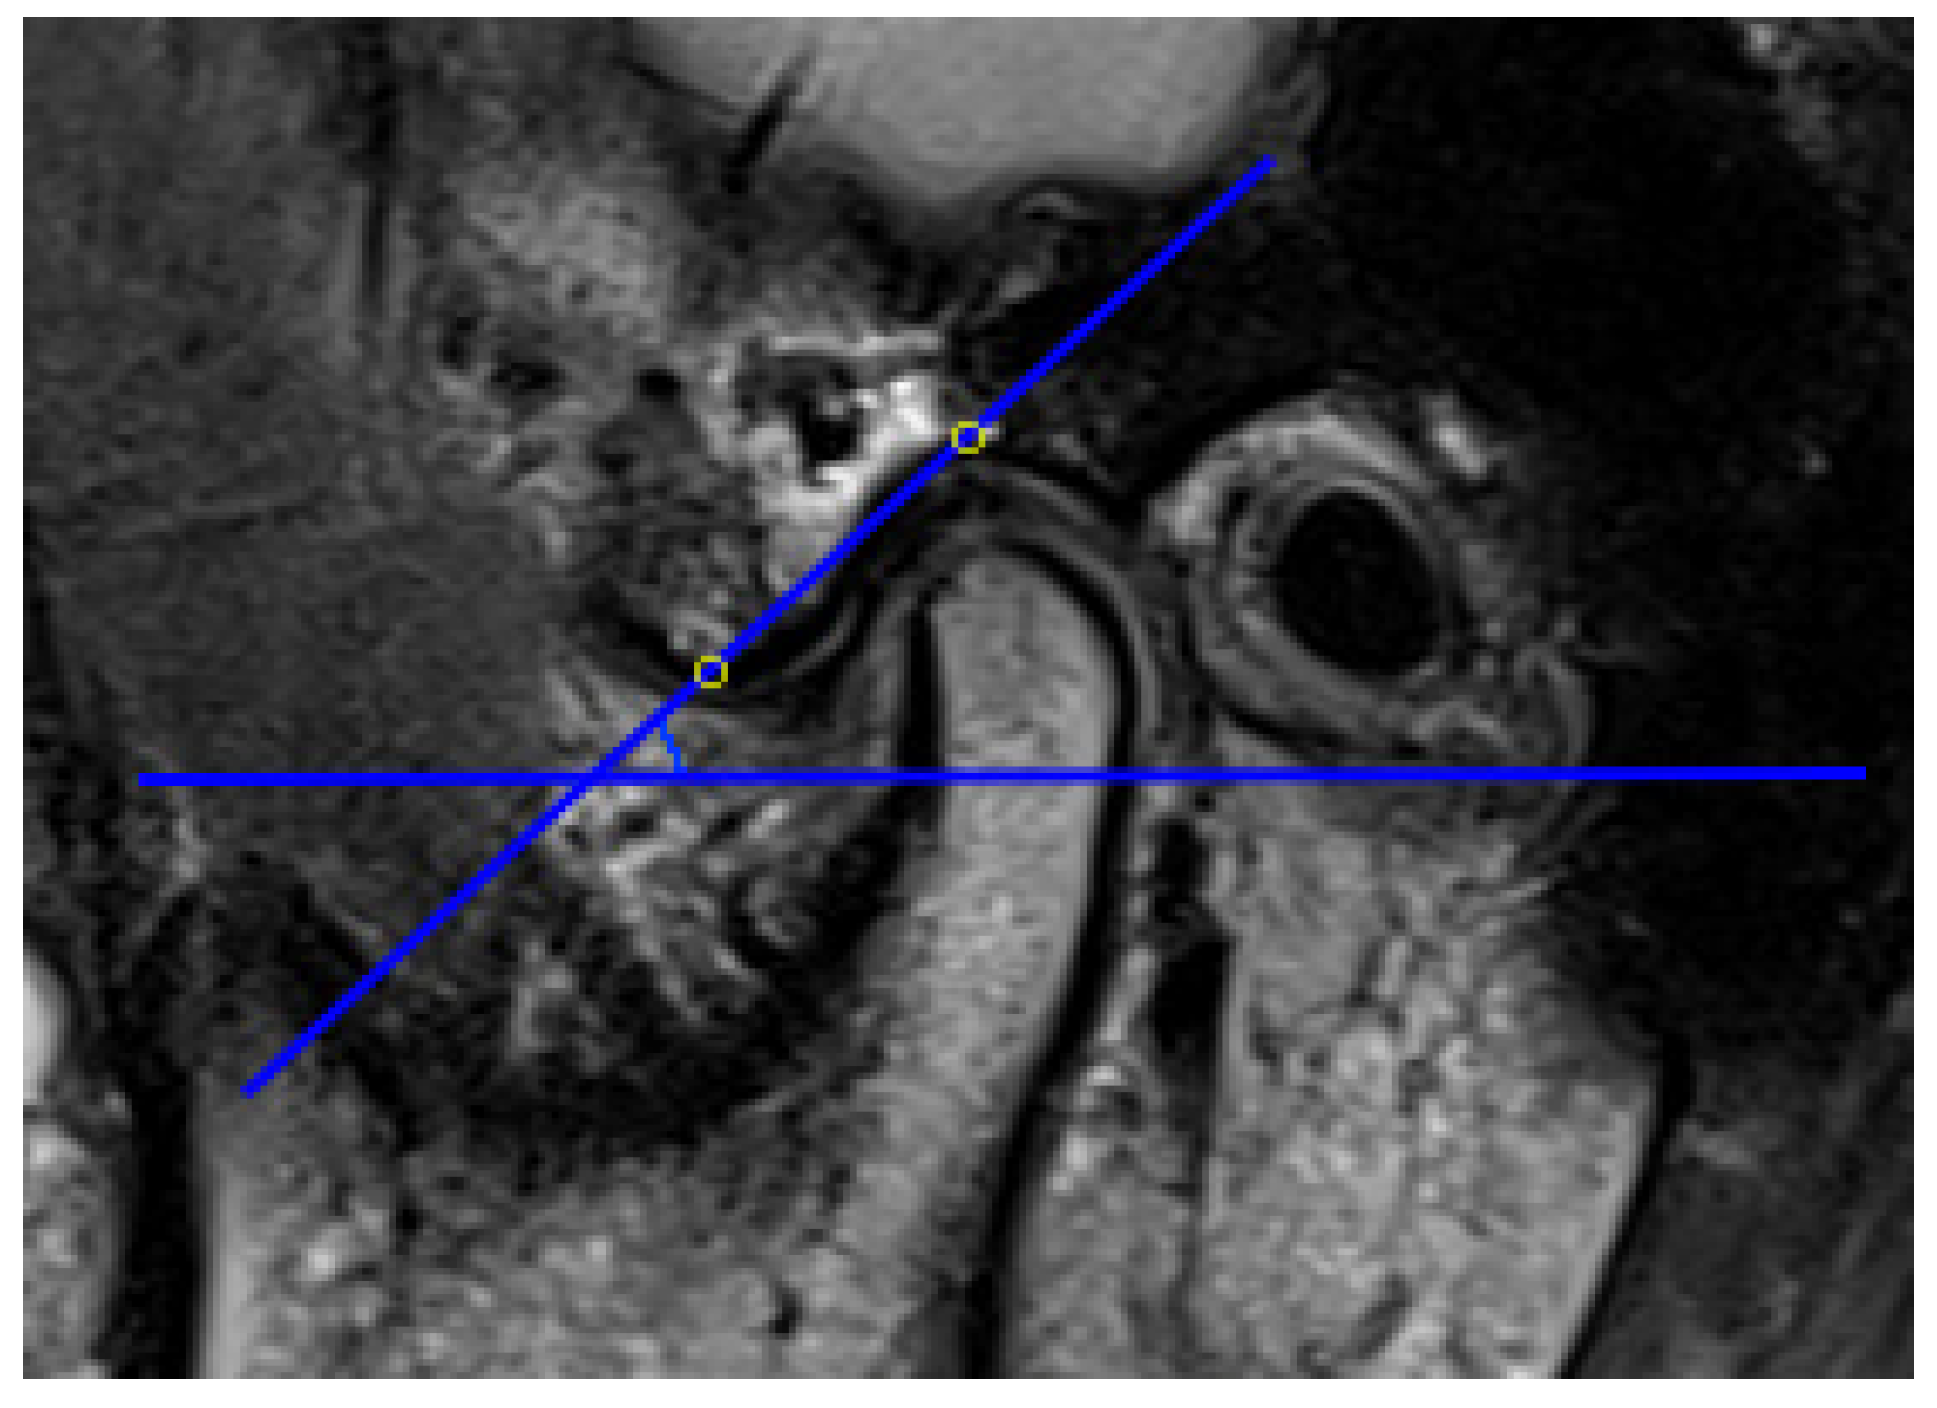

The AEI is defined as the angle formed by one of the lines that passes through the articular eminence and the horizontal reference plane [57]. In previous articles, two main methods have been described for evaluating the AEI, i.e., the “top-roof line” method and the “best-fit line” method, which are reliable and have already been used in studies. The “top-roof line” is obtained by connecting the crest point of the articular eminence and the roof of the mandibular fossa (Figure 2). The angle between the “top-roof line” and the horizontal reference plane is related to the height of articular eminence, which focuses on the localization of the tubercle in relation to the mandibular fossa and depicts the morphology of articular eminence better. The “best-fit line” method was defined as the angle between the tangent line drawn to the posterior slope of the articular eminence and the horizontal reference plane, which is directly related to the movement direction of the condyle-disk complex and reflects the actual condylar path (Figure 3) [26,30,31,41,57,58]. Five of 16 articles selected in this systematic review used the “top-roof line” method [14,17,18,43,49]; eight articles used the “best-fit line” method [19,20,40,41,42,45,46,48]; two articles used both the “top-roof line” method and the “top-roof line” method to evaluate the AEI [3,47], and the other article used the angle between tangent line from the uppermost point of the glenoid fossa and the true horizontal line as AEI [44]. Although the three mentioned methods all represent the inclination of the articulator eminence, the features they focus on are different. Therefore, they should be considered separately.

Figure 2.

Representative images of “top-roof line” method, the articular eminence inclination (AEI) defined as the angle between the line connecting the crest point of the articular eminence and the roof of the mandibular fossa and the horizontal reference plane.